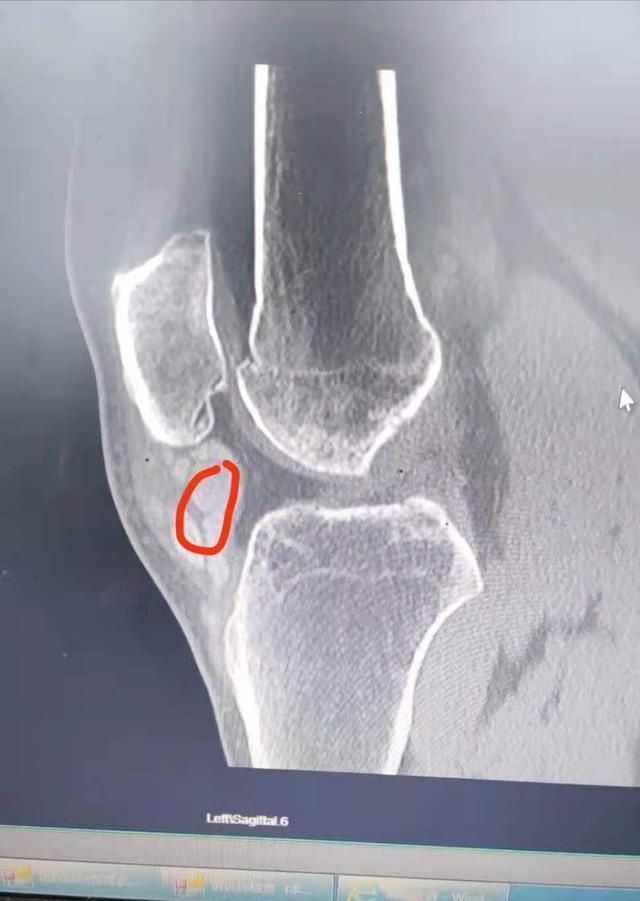

“这是我从医以来,见过的尿酸最高的患者”,武汉市第四医院运动医学科张绍华医生,忍不住发了一条朋友圈:患者尿酸高达856(正常参考值在208-424),多处关节积满了痛风结晶,膝关节严重肿胀已不能弯曲,手术打开后软骨已经严重磨损,大量痛风结石磨成呈石灰膏状。

但近段时间他发现,右脚膝关节肿起了一个包块,越来越大已经导致腿部不能弯曲。到外院检查怀疑是良性肿瘤病变,经人介绍到武汉市第四医院运动医学科,仔细检查后排除肿瘤可能,原来是髌腱下方长了一颗巨大的痛风石。不仅如此,在他的手部、膝关节、踝关节等部位,都发现不同程度的痛风结石。由于长期尿酸高,其肝功能也受损严重。

随即,胡师傅在该院运动医学科接受了外科手术,张青松主任专家团队打开膝关节后发现,关节软骨已被痛风结石覆盖,长期摩擦导致大量痛风结石被磨成石灰膏状,经仔细清理后,关节恢复了正常活动功能。